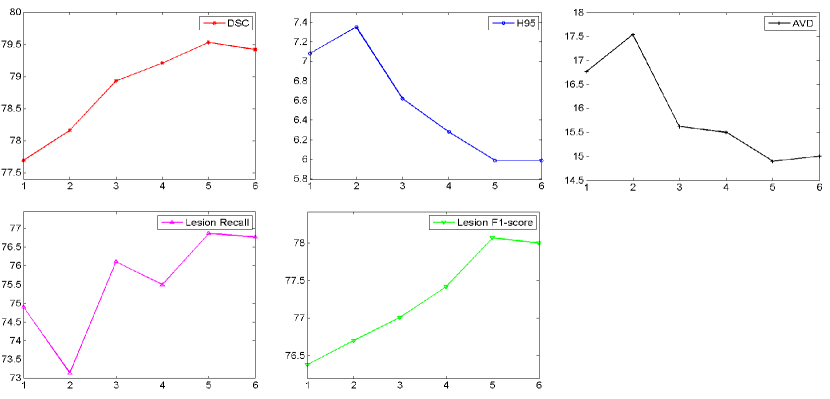

5.6 Effect of the size of ensembles

Ensemble learning aims at aggregating different models to boost the segmentation performance. The optimal size of an ensemble, i.e., how many models in the ensemble are needed, still remains an open issue and, as in many related ensemble learning task, a task specific parameter that needs to be optimized. To this end, we evaluated how the segmentation performance behaves over the number of ensemble models. We split the public dataset into training set and validation set by randomly picking 80% and 20% cases from each scanner respectively. The models were trained on 48 cases and validated on 12 cases. Then the segmentation performance on 12 cases were averaged on each evaluation metric. For each model with different size of ensembles, the training process was repeated five times and the segmentation results on the validation set were averaged.

Figure 13 shows the curves of segmentation performance on five metrics w.r.t different ensemble size. It could be seen that (1) the ensemble with three or more models clearly outperformed the ensemble of only one model on all of the five metrics. The improvement of ensemble model with size over one with size is statistically significant on five metrics, all with small p-values; (2) when the size was further increased, performance tended to saturate and minor improvements in some of the measures came at the cost of small decreased in others. Figure 14 shows standard deviation of segmentation performance between five repeated trained models w.r.t different ensemble size. It could be observed that the variation of segmentation performance was reduced on the main evaluation metrics when the size of ensemble was increased. It demonstrated that the ensemble model can not only boost the segmentation performance but also guarantee a robust segmentation result. Figure 15 shows a case segmented by three individual models and their ensemble. We observed that three models trained with different weights initializations and shuffled data generated significantly different result on boundary and small lesions. And the model ensemble avoided the worst segmentation result.